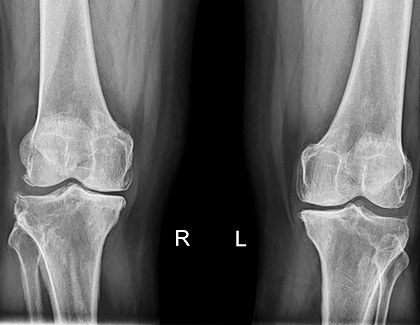

Diz Kireçlenmesi Ameliyatsız Tedaviler

Diz kireçlenmesi (osteoartrit), diz ekleminde kıkırdak aşınması sonucu ağrı ve hareket kısıtlılığına yol açan yaygın bir rahatsızlıktır. Ameliyatsız tedavi seçenekleri, hastaların ağrılarını hafifletmek ve yaşam kalitesini artırmak için etkili bir çözüm sunar. Fizik tedavi ve rehabilitasyon programları, diz çevresindeki kasları güçlendirerek ekleme binen yükü azaltır. Platelet Rich Plasma ve hyaluronik asit enjeksiyonları, eklem sağlığını destekler ve iltihabı azaltır. Ayrıca, kişiye özel hazırlanan egzersiz programları, kilo kontrolü ve ergonomik yaşam önerileriyle semptomların kontrol altına alınması hedeflenir. Erken müdahale ve düzenli tedavi ile diz kireçlenmesinde başarılı sonuçlar elde edilebilir.